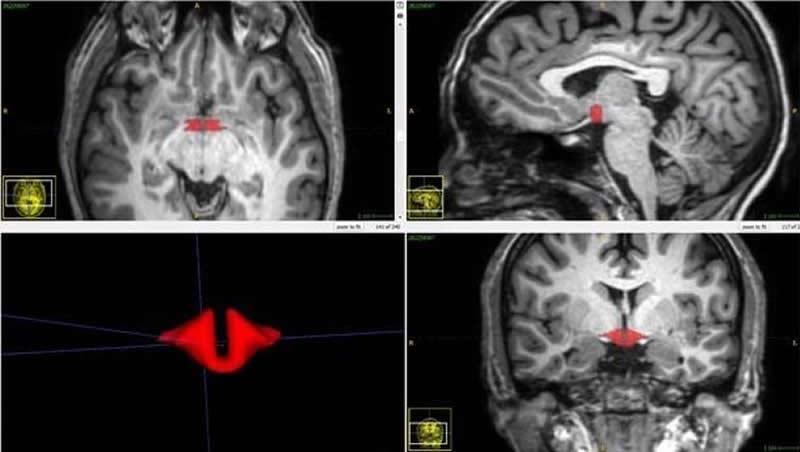

Summary: A new neuroimaging study reveals women who take oral contraception have reduced hypothalamic volume compared to women who do not take the pill. Smaller hypothalamic volume was associated with increased negative emotions and depression risk.

Located at the base of the brain above the pituitary gland, the hypothalamus produces hormones and helps regulate essential bodily functions including body temperature, mood, appetite, sex drive, sleep cycles and heart rate.

“There is a lack of research on the effects of oral contraceptives on this small but essential part of the living human brain,” said Michael L. Lipton, M.D., Ph.D., FACR, professor of radiology at the Gruss Magnetic Resonance Research Center at Albert Einstein College of Medicine and medical director of MRI Services at Montefiore Medical Center in New York City. “We validated methods for assessing the volume of the hypothalamus and confirm, for the first time, that current oral contraceptive pill usage is associated with smaller hypothalamic volume.”

In his study, Dr. Lipton and colleagues recruited a group of 50 healthy women, including 21 women who were taking oral contraceptives. All 50 women underwent brain MRI, and a validated approach was used to measure hypothalamic volume.

“We found a dramatic difference in the size of the brain structures between women who were taking oral contraceptives and those who were not,” Dr. Lipton said. “This initial study shows a strong association and should motivate further investigation into the effects of oral contraceptives on brain structure and their potential impact on brain function.”

The image is credited to the study author and RSNA.